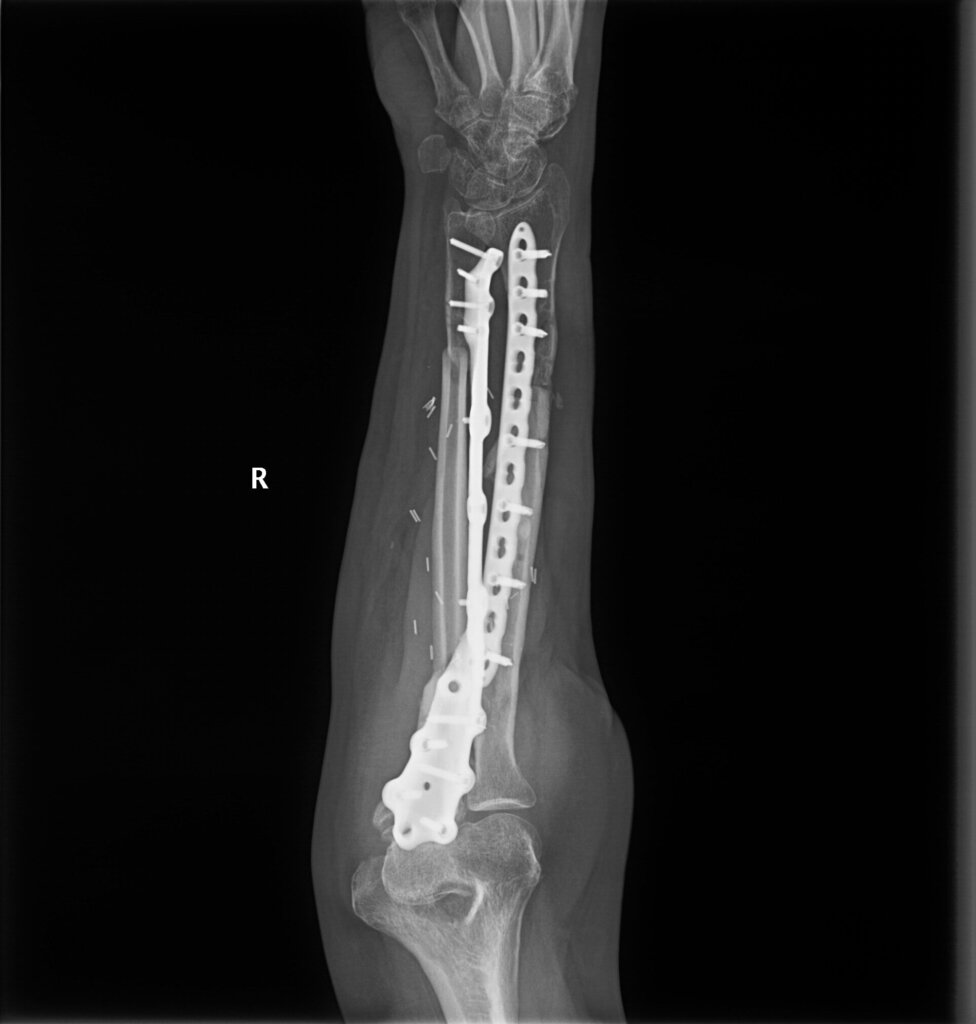

Согласно данным анамнеза и медицинской документации, пациент М. 49 лет получил огнестрельное осколочное ранение правой верхней конечности. Первая помощь оказана на месте. При поступлении в медицинский отряд пациенту выполнено рентгенологическое исследование правого предплечья. Выявлено: открытый многооскольчатый перелом нижней трети диафиза правой лучевой кости со смещением костных отломков, многооскольчатый перелом верхней и средней трети диафиза правой локтевой кости со смещением и дефектом костной ткани. Выполнена первичная хирургическая обработка ран правого предплечья и фиксация костей предплечья в АВФ КСВП1. На этапах эвакуации пациенту проводились этапные хирургические обработки до заживления ран предплечья.

Через 3 месяца после травмы пациент был переведен в травматологический центр, где после клинико-диагностического обследования установлен диагноз: последствия огнестрельного осколочного ранения правой верхней конечности от сентября 2022 года в виде консолидирующегося в неправильном положении многооскольчатого перелома нижней трети диафиза правой лучевой кости, многооскольчатого перелома верхней и средней трети диафиза правой локтевой кости со смещением и дефектом костной ткани. Посттравматическая нейропатия лучевого нерва.

В связи с наличием рубцовой деформации и дефицита мягких тканей правого предплечья, дефекта правой локтевой кости до 10 см, было принято решение о проведении оперативного лечения в объеме пластики дефекта мягких тканей и локтевой кости свободным малоберцовым трансплантатом с фиксацией индивидуальной 3D-пластиной, металлоостеосинтеза лучевой кости правого предплечья пластиной. В рамках предоперационного планирования пациенту была выполнена компьютерная томография, на основе которой создан макет индивидуальной конструкции (рисунок 2).

На 95 сутки после ранения проведена реконструктивно-пластическая операция: пластика дефекта мягких тканей и локтевой кости правого предплечья свободным кожно-фасциально-костным малоберцовым лоскутом с фиксацией индивидуальной 3D пластиной, металлоостеосинтез лучевой кости правого предплечья пластиной.

На контрольных рентгенограммах КТ через 4 месяца после реконструктивно-пластической операции отмечается полная перестройка малоберцового трансплантата, замещенного дефекта.